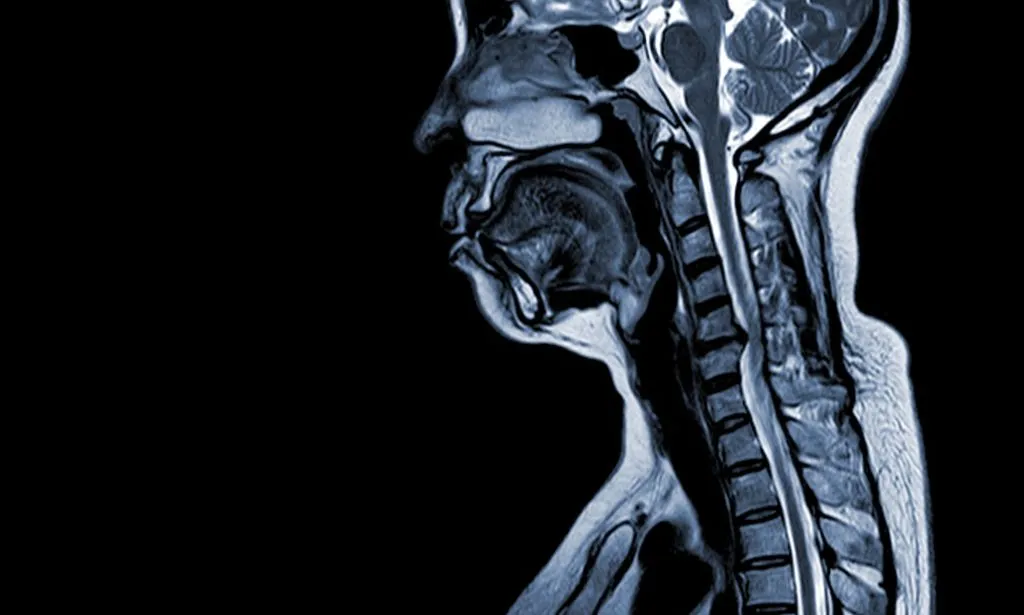

Herniated Disc In Neck MRI

A herniated disc in neck MRI provides the clearest view of spinal disc injuries, making it the most effective tool for diagnosing cervical disc herniations.

An MRI (Magnetic Resonance Imaging) uses powerful magnets and radio waves to produce detailed images of the spine, allowing doctors to visualize herniated discs accurately.

During the scan, patients lie still inside the MRI machine, which captures cross-sectional images of spinal discs and surrounding tissues. This helps reveal annular tears, disc herniations, inflammation, and other conditions contributing to chronic neck pain.

On an MRI, a herniated disc appears as a bulging or displaced section of the intervertebral disc material that extends beyond its normal boundaries.

In T2-weighted images, which highlight fluid content, the herniation is often visible as a dark mass against the brighter cerebrospinal fluid, indicating a disruption in the disc’s normal structure.

The severity of the herniation can vary, ranging from a minor bulge to a full extrusion where disc material has leaked out.